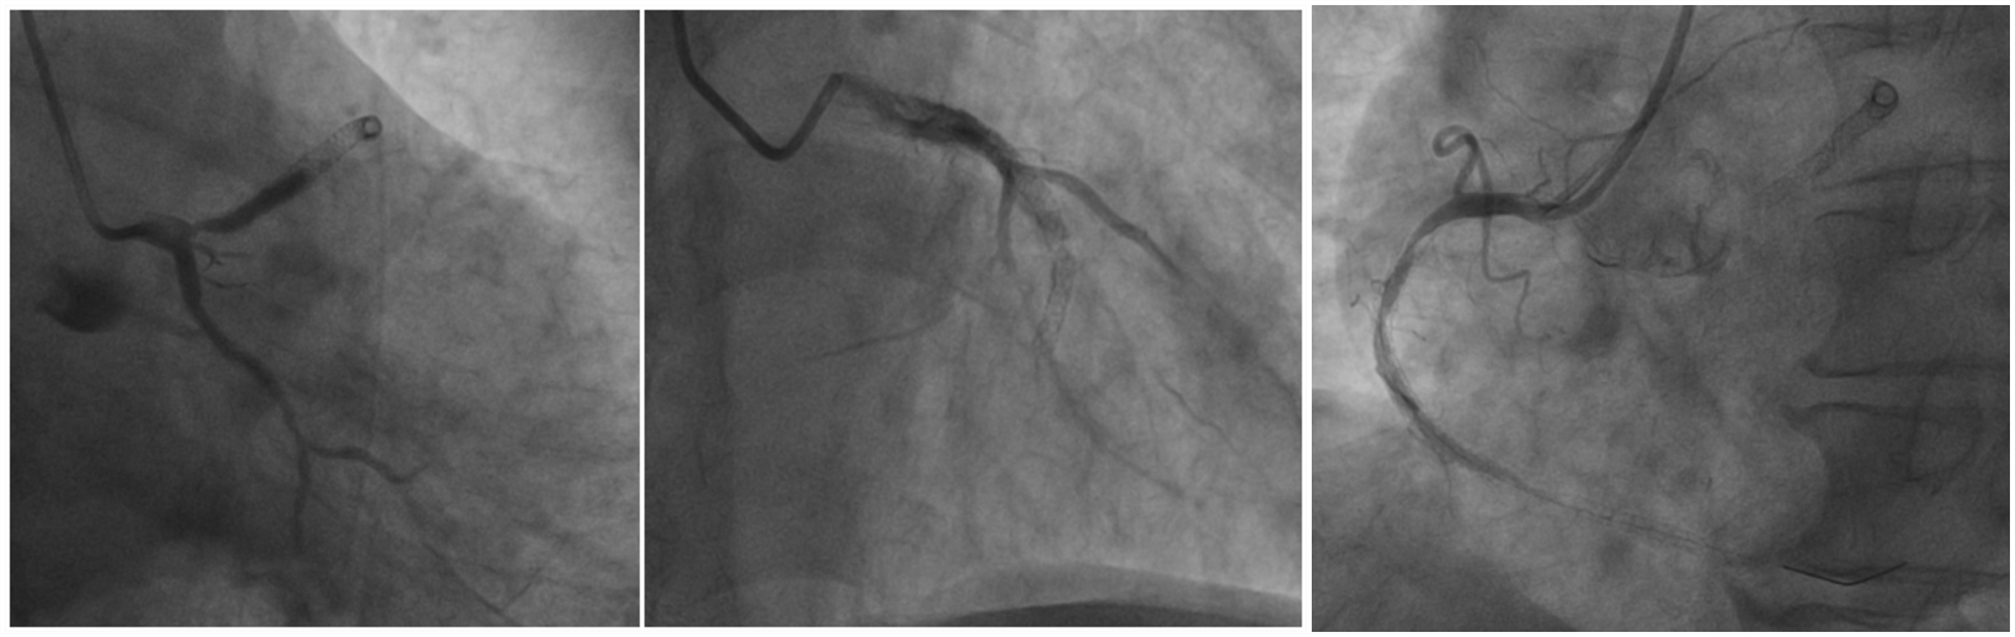

冠脉造影完成,前降支(LAD)近段90%弥漫狭窄,前向血流TIMI0级;回旋支(LCX)硬化,前向血流TIMI1-2级。右冠脉(RCA)近段75%狭窄、中段闭塞,前向血流TIMI0级。(图2)。

图2. 左冠造影结果

在按压的同时完成手术已是不易,选择正确的手术顺序尤为重要。生死就在一念之间,王乂的选择超乎在场所有人的意料,他要先处理LAD!

“王哥,这是下壁心肌梗死,右冠闭塞是罪犯血管啊。”助手有些紧张的问“这我能不知道?!”王乂的声音不大,但是有些吓人,尤其是那双眼睛,快要喷出火来。一时间,再没人敢说话,只看到王乂不断操作:LAD病变处2.0*15mm球囊以12atm预扩张,造影后可见残狭减轻,血流改善,LCX血流也同时改善,均达TIMI3级。将3.5*14mm支架至LAD病变处以16atm扩释,造影后未见明显残余狭窄及夹层,前向血流TIMI3级。(图3)

图3. 左冠术后状况